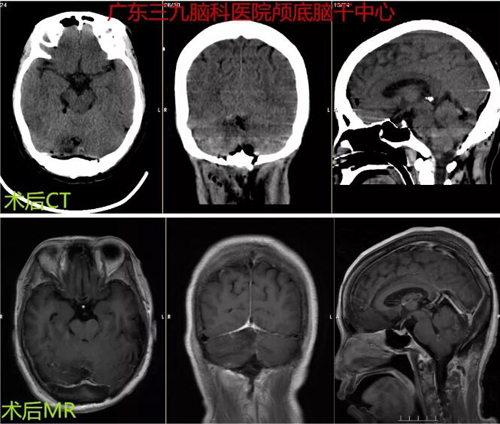

图3:术后CT及MR示右侧枕部占位性病变切除术后改变,原病变已切除